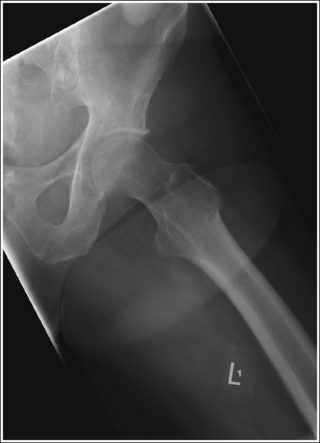

• Positioning for a fractured or dislocated proximal femur. When a patient has a dislocated or fractured proximal femur, the leg should not be internally rotated but left as is. Forced internal rotation of a dislocated or fractured proximal femur may injure the blood supply and nerves that surround the injured area. Because the patient's leg is not internally rotated when a fracture is suspected, the resulting AP hip projection may demonstrate the femoral neck with some degree of foreshortening and the lesser trochanter without femoral shaft superimposition (see Image 5).

IMAGE 5

IMAGE 14

• Positioning for a proximal femoral fracture or dislocation. When a patient has a dislocated hip or a suspected or known proximal femoral fracture, the leg should not be internally rotated, but left as is. Forced internal rotation of a dislocated hip or fractured proximal femur may injure the blood supply and nerves that surround the injured area. Because the patient's leg is not internally rotated in such cases, it is acceptable for the greater trochanter to be demonstrated posteriorly and the lesser trochanter to be superimposed over the femoral shaft (see Image 15).

IMAGE 15

Soft tissue from the unaffected thigh is superimposing the acetabulum and femoral head of the affected hip. The unaffected leg was not adequately flexed or abducted.

Flex and abduct the unaffected leg, drawing it away from the affected acetabulum and femoral head. If the patient is unable to adjust the unaffected leg further, the kVp and mAs can be increased to demonstrate this area. A wedge-type compensating filter may also be added to prevent overpenetration of the femoral neck and shaft.

The greater trochanter is demonstrated posteriorly, and the lesser trochanter is superimposed over the femoral shaft. The patient's affected leg was in external rotation.

Internally rotate the patient's leg until the femoral epicondyles are aligned parallel with the imaging table and the foot is angled internally 15 to 20 degrees from vertical, as shown in Figure 7-18.